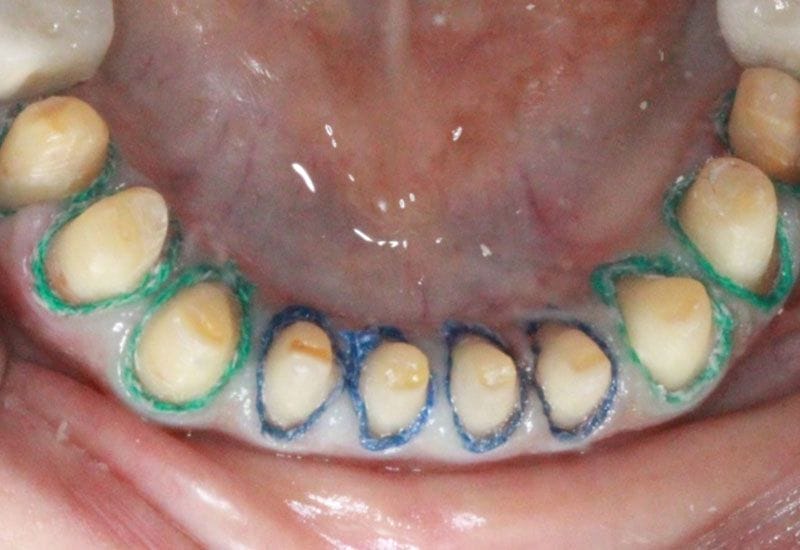

因為下頷後牙缺牙,蕭小姐尋求下頷後牙植牙治療,由於口內其他牙齒均因蛀牙或過度磨耗呈現齒質鬆軟崩裂等現象,不但影響美觀,對於咀嚼也造成不便,加上磨耗的牙齒有酸軟無力現象,因此蕭小姐決定除了下頷後牙植牙治療外,其他牙齒的假牙重建也一併處理。

如圖1.2.3.4.5

圖1